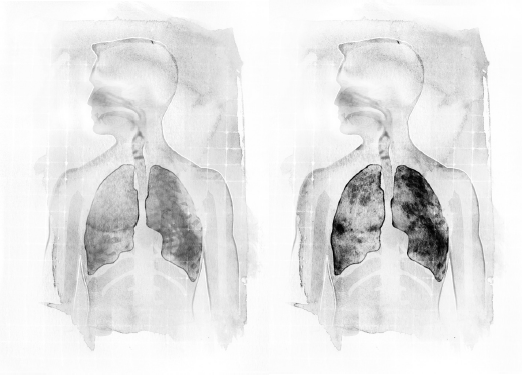

无论在世界上的哪个地方,呼吸失调都是疾病的主因之一。单以气喘来说,罹患的人口有二亿三千五百万之多—这个数字还在持续攀升中。肺病和呼吸失调的原因复杂无比,许多事情都可能引发疾病,包括灰尘、污染、对动物的毛过敏等等。

在许多案例中,无论致病的原因是什么,改进呼吸方式都能对病情带来相当程度的助益。即使是没被医生诊断出呼吸疾病的人,也可能因为姿势习惯不良而呼吸效能低落,导致日后在呼吸方面出现问题。

在现代社会中,只有极少数人是以自然的方式在呼吸—太多人忙得不可开交,生活犹如一场旋风,整天东奔西跑;有时身体虽然没在动,手上的工作却仍旧赶个不停,例如忙于使用电脑。「疾速时代」的生活压力使得人们养成呼吸不良的习惯,究其原因,当我们感受到时间的催逼时,呼吸几乎都会变快、变浅,然而这对身体并非好事。事实上,翻腾在我们脑海里的事情会对呼吸产生影响。当我们心中感到害怕时,呼吸和心跳会加速;如果我们突然吃了一惊,或是在路上捡到某样奇怪的东西,呼吸往往会不自觉地憋起来。

这一代的人要处理的日常事务很繁杂,比起祖父母的那一代绝对大有过之,结果就是呼吸深受其害。现代人所面临的生活刺激以各式各样的面貌呈现出来,包括智慧型手机、平板电脑、电视、电子邮件、庞大的车流量、逼人太甚的工作期限等等。这些生活刺激有如砲弹一般,每天不断向我们轰炸而来,无疑对我们的呼吸带来了巨大的影响。

日常的姿势、行走步调也是影响呼吸方式的主因。人们站立、坐下、走路的方式可能造成肌肉过度拉紧,但那些紧绷其实毫无必要。一个人如果习惯于绷紧肌肉,时日一久,注定会养成不良的呼吸方式,使得呼吸的自然反射受到妨碍。在学校接受教育的一、二十年当中,学生们弯腰驼背地坐在书桌前面学习,到了毕业离校之日,呼吸方式没产生恶性变化的人实在少之又少—然后我们更换地点,继续弯腰驼背,坐在电脑前面。

姿势不良可能使身体畸形到某种程度,导致胸腔窄缩,因而拘束到肋骨和肺脏的活动空间。容纳呼吸器官的空间不足时,人体会被迫采取比较短浅的呼吸,用力去吸取身体需要的空气。

久而久之,这种呼吸方式会形成习惯,让当事人觉得十分正常。对呼吸而言,身体姿势是个无比重要的因素,这一点会在第十章细谈。

时至今日,许多人的呼吸习惯是不良的,可是没几个人自觉在呼吸方面出了毛病。只要改变目前的呼吸方式,便可以为自己的将来节省许多时间和麻烦。

在世界各地,抽烟是导致疾病和死亡的主因之一,然而这类疾病和死亡其实是可以预先防范的。在阻塞性肺病的病例中,80%至90%是因为患者抽烟而直接致病的;至于肺癌,90%的患者是因为抽烟而直接致死。

瘾君子的肺脏会随着抽烟时间拉长而功能越来越差。前面介绍到数种阻塞性肺病,不论是罹患哪一种阻塞性肺病,患者有两类典型,一类是年纪很轻就开始抽烟,另一类是烟瘾很大。随着阻塞性肺病的症状越来越糟,患者的呼吸会越来越困难,即便只是进行日常活动,他们也会感到筋疲力竭,于是他们的活动量逐渐降低。到了病情严重的时候,患者可说是名符其实的形容枯槁,因为他们连吃个饭、喝个水都要耗尽全力。

用浅白的话来说,抽烟会破坏肺脏的弹性。暴露于香烟和其他环境毒物是导致阻塞性肺病的主因,只要减少抽烟量,就可以把症状控制住,轻松改善呼吸道的健康;如果能够彻底戒烟的话,那就更好了。此外,避免吸入二手烟和其他空气毒素也同样重要,而运动、干净的空气、健康的饮食对病情都能带来益处。